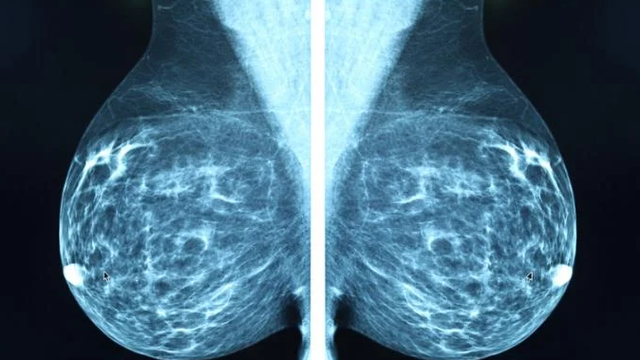

Studiuesit nga MIT kanë zhvilluar një sistem të avancuar të inteligjencës artificiale të quajtur “Mirai”, i cili synon të parashikojë rrezikun e zhvillimit të kancerit të gjirit në pesë vitet e ardhshme.

Sistemi analizon imazhet e mamografisë duke i koduar dhe përmbledhur me të dhëna të tjera, ndërkohë që merr në konsideratë edhe faktorët tradicionalë të rrezikut si mosha dhe historia familjare. Kështu, krijohet një vlerësim individual dhe i personalizuar për secilën paciente. Krahasuar me modelet ekzistuese, Mirai ka treguar saktësi më të madhe dhe qëndrueshmëri në parashikim, pavarësisht nga grupi racor, dendësia e gjirit apo mosha e pacienteve.

Pas testimeve të suksesshme në SHBA, Suedi dhe Tajvan, Mirai arriti të identifikojë pothuajse dyfishin e rasteve të mundshme të kancerit të gjirit. Aktualisht, ekipi i MIT është në bashkëpunim me spitale ndërkombëtare për ta futur këtë teknologji në përdorim të përditshëm, duke kontribuar në zbulimin më të hershëm të kancerit dhe reduktimin e ekzaminimeve të panevojshme.